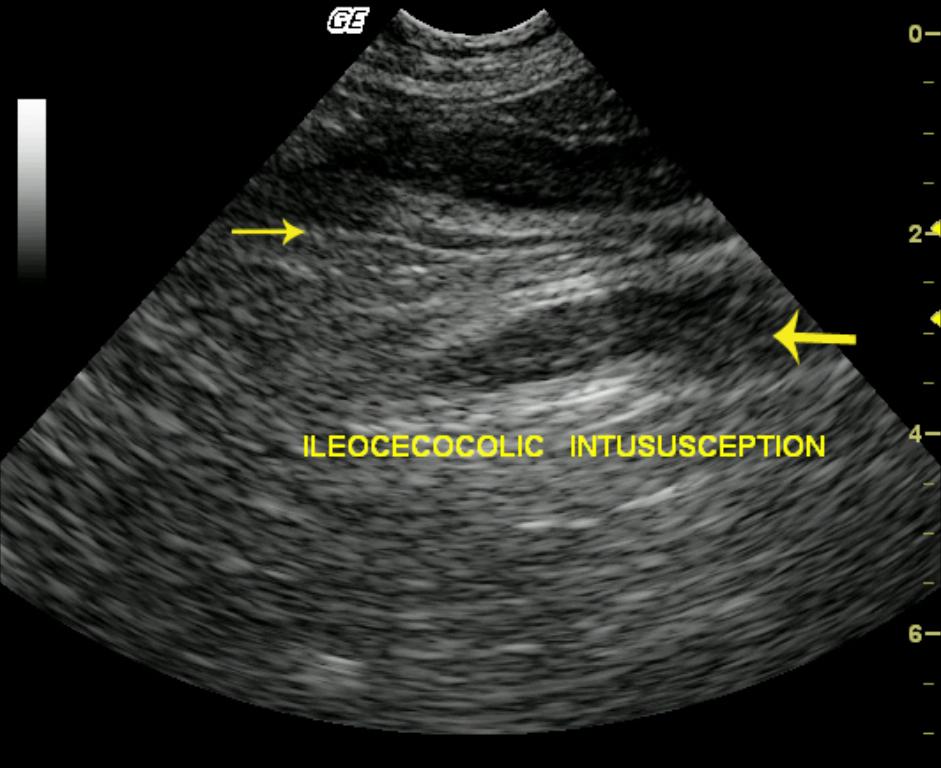

This 16-year-old MN DSH cat presented for postprandial vomiting as well as diarrhea, weight loss, anorexia, and tenesmus. The physical examination revealed ropey intestines on abdominal palpation. A CBC and blood chemistry profile revealed a moderate neutrophilia with a left shift and normal chemistry values.